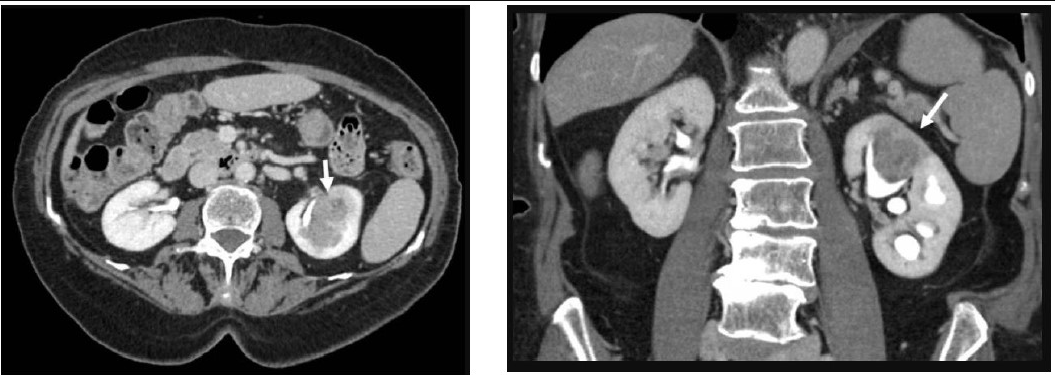

• CT Urography: High-resolution computed tomography (CT) scans visualize the urinary tract, providing detailed images of the kidneys, ureters, and bladder.

Upper Tract Urothelial Cancer (UTUC) stands out as a distinct entity from kidney cancer, primarily originating in the urothelial lining of the renal pelvis and ureter. Unlike kidney cancer, which encompasses various types of malignancies affecting the kidney, UTUC specifically involves the upper urinary tract. This cancer, while relatively rare compared to other urological malignancies, presents a unique set of challenges due to its anatomical location. UTUC can manifest as either renal pelvis or ureteral cancer, and it shares histological similarities with bladder cancer. The presentation may include symptoms such as hematuria (blood in urine), flank pain, and hydronephrosis. Diagnostic approaches involve imaging studies like CT urography and ureteroscopy, often followed by biopsy confirmation. UTUC's distinct location requires tailored treatment strategies that consider tumor stage, grade, and the patient's overall health.